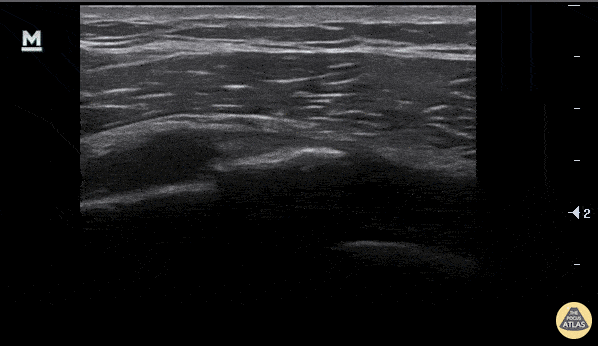

A rib fracture is seen here as disruption in the hyperechoic line or bony cortex. Also note the associated hypoechoic hematoma formation. Aaron Inouye, PA-C, North Canyon Medical Center @PAintheED